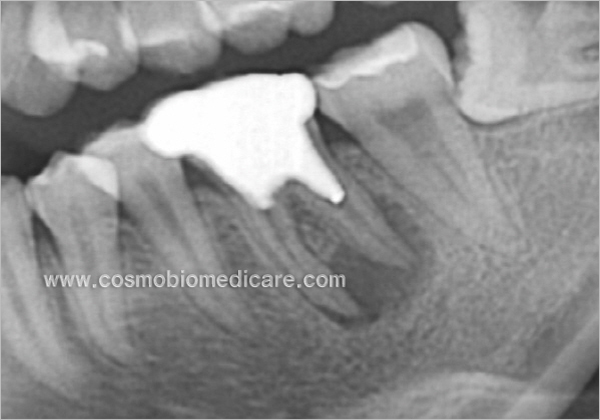

Clinical Cases

• Case1